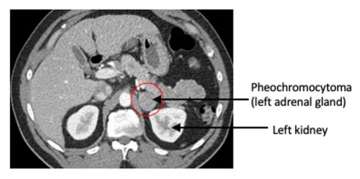

Anyone with an adrenal nodule discovered on imaging (e.g. a CT scan or MRI of the abdomen) should have appropriate biochemical work-up to determine if the adrenal nodule is producing excessive hormones. This is done by laboratory testing of the blood and/or urine. Pheochromocytomas have specific imaging characteristics that can be evaluated on CT or MRI.

CT or MRI of the abdomen will almost always identify a pheochromocytoma. Additional specialized imaging such as MIBG (meta-iodobenzylguanidine) or Ga-68 Dotatate PET/CT scan can help to confirm a pheochromocytoma and identify multiple tumors or metastatic spread.